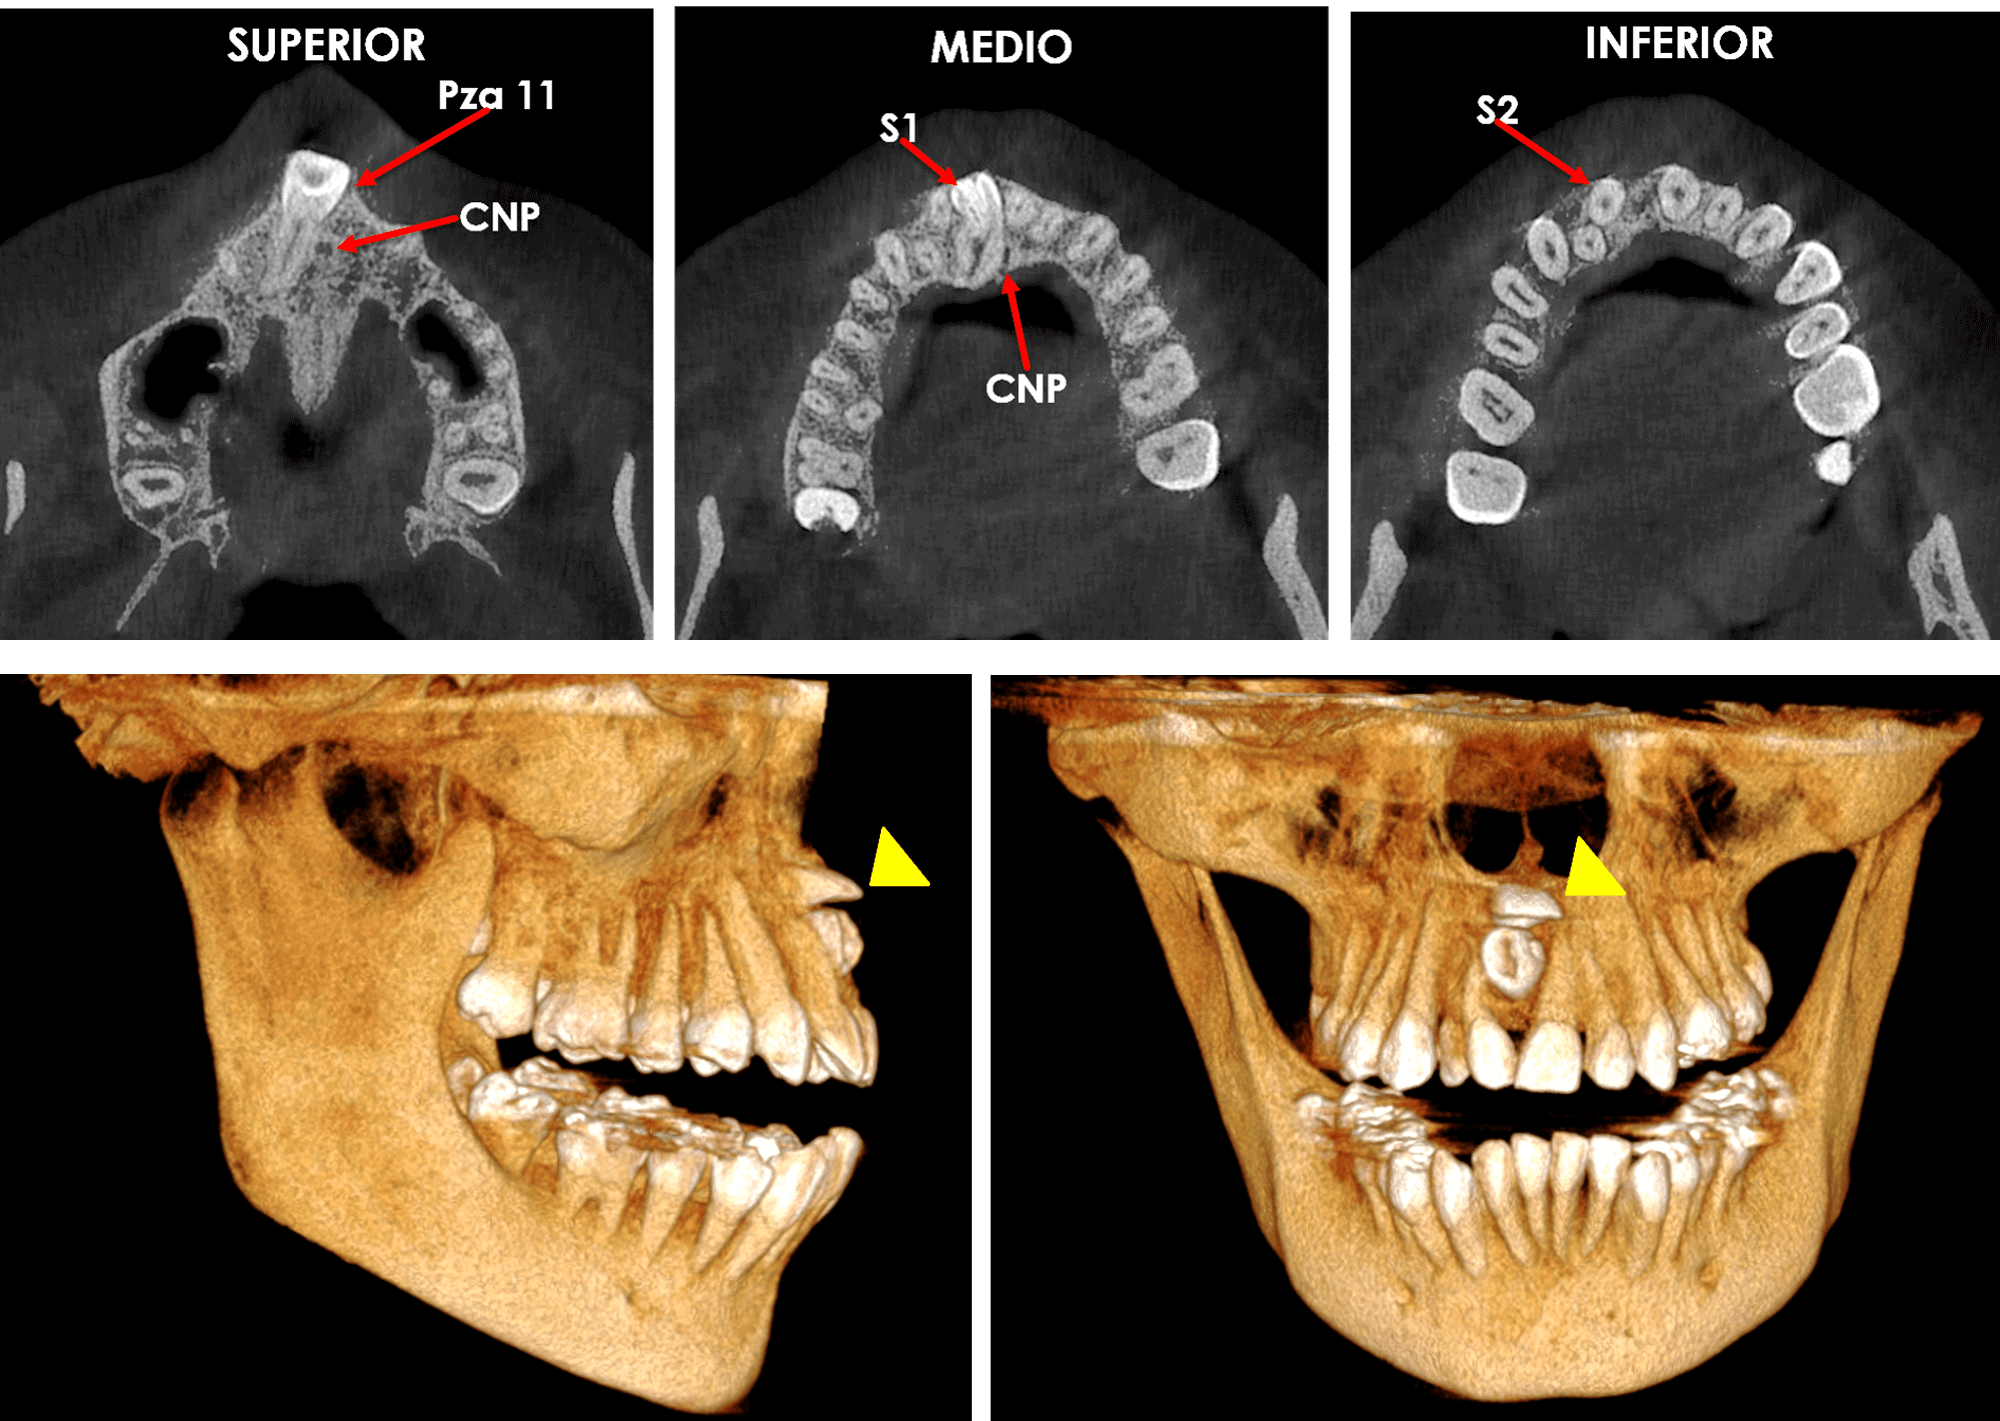

Este equipo avanzado nos ayuda a capturar tomografías en 3D que muestran tanto los dientes como las estructuras óseas cercanas, lo que facilita la detección de problemas dentales complejos, como infecciones, fracturas o dientes impactados. Además, este tipo de imágenes también son útiles para detectar posibles problemas médicos en otras partes del cuerpo, brindándote una atención más completa y segura.

Gracias a la calidad superior de las imágenes en 3D, podemos observar detalles que no serían visibles con equipos convencionales. Esto nos ayuda a detectar problemas desde una etapa temprana y a planificar tratamientos más efectivos, como implantes o cirugías dentales complejas.